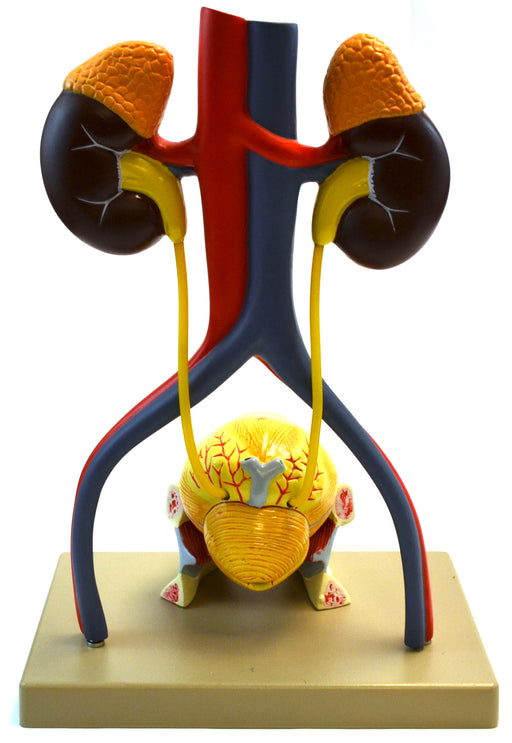

Eisco Life-Size Human Male Urinary System Model, 5 Parts

Approximately life size model includes kidneys with adrenal glands, ureters, urinary bladder, prostate gland, abdominal aorta, inferior vena cava,...

View full detailsAM0356 -